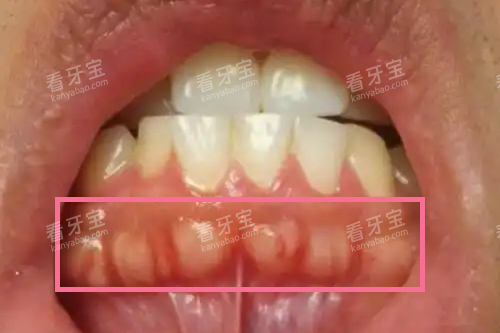

这种增生通常表现为牙龈表面凸起的硬块,表面覆盖的黏膜颜色正常,呈粉红色,触摸时质地坚硬如骨。比较常见的位置是下颌双尖牙的舌侧,形成半球形的舌隆突,也可能出现在双尖牙或磨牙的颊侧,形成较小的骨性突起。很多人是在刷牙或无意间用舌头舔到时才发现这些异常凸起。

牙槽骨增生的外观特征相当明显,但很多人因为不了解而误以为是肉瘤或其他重的问题。以下是几种典型表现:

硬质凸起:比较显著的特征就是在牙龈上摸到一个硬硬的突起,按压不会有疼痛感,与周围牙龈组织界限清晰

表面光滑:增生的牙槽骨表面覆盖的黏膜通常保持正常,颜色粉红,没有溃疡或红肿